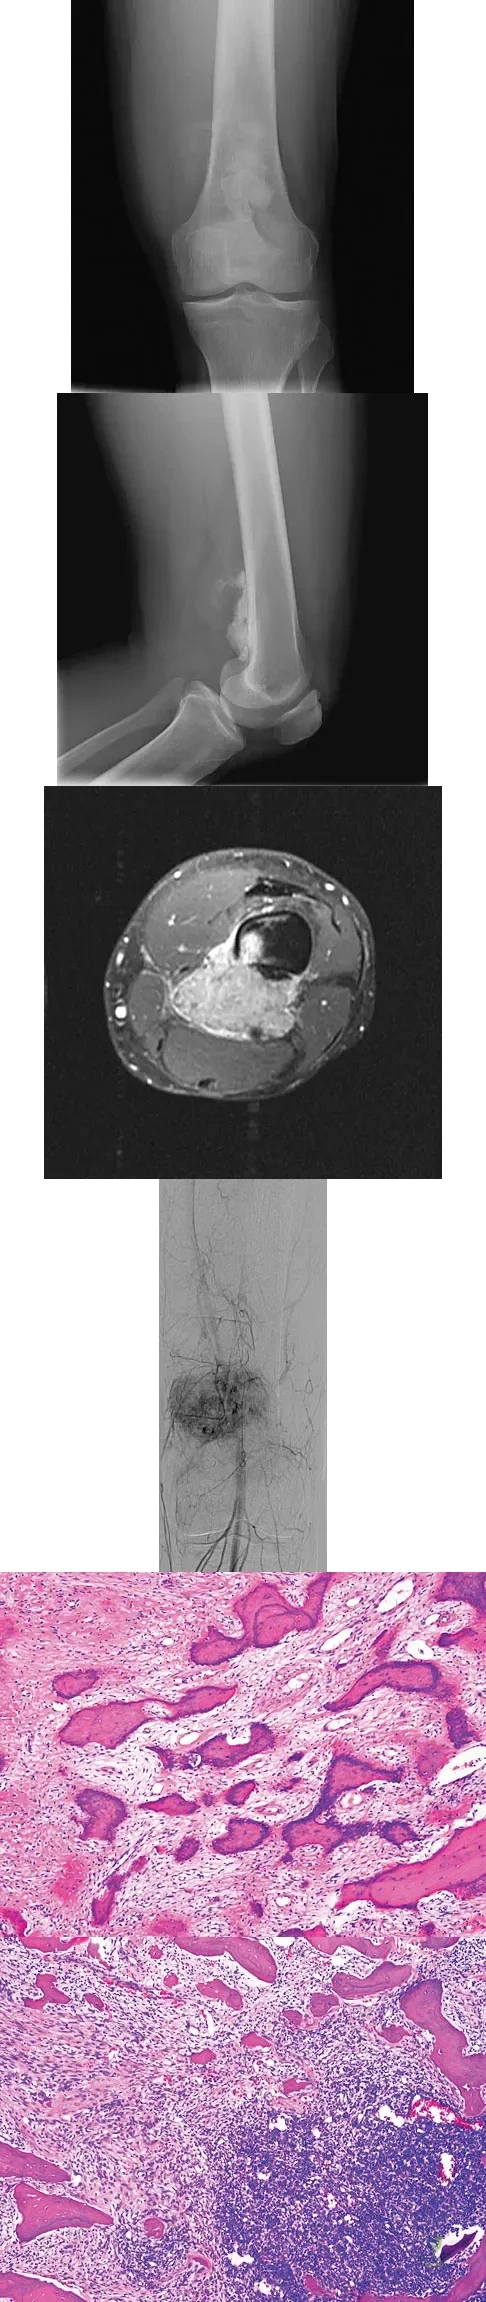

An otherwise healthy 33-year-old man who works in construction reports a 3-month history of knee pain. Radiographs are shown in Figures 9a and 9b. An axial T1-weighted MRI scan with contrast, an angiogram, and histologies are shown in Figures 9c through 9f. What is the most likely diagnosis?